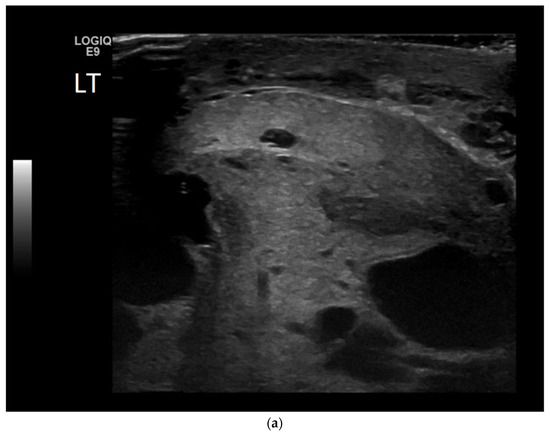

4.2. Non-Seminomatous Germ Cell Tumour (NSGCTs)

| Non-seminomas | Heterogenous Irregular margins Cystic and calcification components seen commonly |